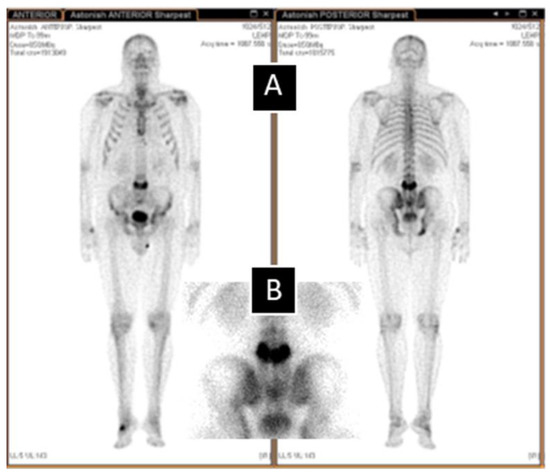

- Kesim, S.; Turoğlu, H.T.; Özgüven, S.; Öneş, T.; Erdil, T.Y. Mickey Mouse Sign on Bone Scan in the Monostotic Form of Paget’s Disease Mimicking Osseous Metastasis. Mol. Imaging Radionucl. Ther. 2020, 29, 132–134. [Google Scholar] [CrossRef] [PubMed]

- Rotés-Sala, D.; Monfort, J.; Solano, A.; Miralles, E.; Vila, J.; Carbonell, J. The clover and heart signs in vertebral scin-ti-graphic images are highly specific of Paget’s disease of bone. Bone 2004, 34, 605–608. [Google Scholar] [CrossRef]

- Van Heerden, B.B. Mickey Mouse sign in Paget’s disease. J. Nucl. Med. 1994, 35, 924–925. [Google Scholar] [PubMed]

- Kim, C.K.; Estrada, W.N.; Lorberboym, M.; Pandit, N.; Religioso, D.G.; Alavi, A. The “mouse face” appearance of the verte-brae in Paget’s disease. Clin. Nucl. Med. 1997, 22, 104–108. [Google Scholar] [CrossRef] [PubMed]